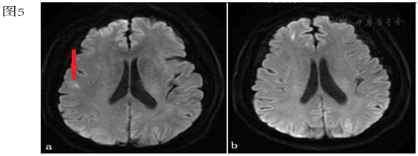

行心电图:窦性心律,T波改变;急查血常规、凝血功能、降钙素原、心肌损伤标记物、BNP未见明显异常。血气分析:酸碱度7.345,二氧化碳分压45.7 mmHg,氧分压74.4 mmHg,乳酸2.1 mmol/L;胸部CT提示:左心室腔可疑气体影(图2)。颅脑CT未见异常,急诊颅脑MRI示:左侧额颞顶枕叶、右侧额顶叶及其皮层下、左侧小脑半球多处新发脑梗死灶(图3a、图4a、图5a)。颈动脉超声:双侧颈动脉内膜增厚。患者同日转入ICU进一步治疗,入室体格检查:T 37.8℃,P 87次/分,R 15次/分,BP 190/109 mmHg,鼻导管吸氧,血氧饱和度98%。浅昏迷状态,GCS评分:E2V2M4,双侧瞳孔等大等圆,直径约2 mm,光反射迟钝。双肺听诊呼吸音清,心脏听诊律齐,未闻及杂音及额外心音。四肢肌张力增高,双侧巴氏征阳性。

本例患者,老年女性,体检发现右肺结节,为明确诊断行CT引导下肺穿刺活检术,术后出现意识改变、肌力下降、肢体抽搐等症状,胸部CT示左心室腔可疑气体影;颅脑MRI示多发新鲜脑梗。双侧颈动脉超声未见狭窄或斑块,既往无房颤病史,暂不支持脑栓塞及脑血栓形成。结合患者穿刺后出现症状、体征及影像学检查,科室内共同讨论后,考虑空气栓塞导致脑梗死不除外。